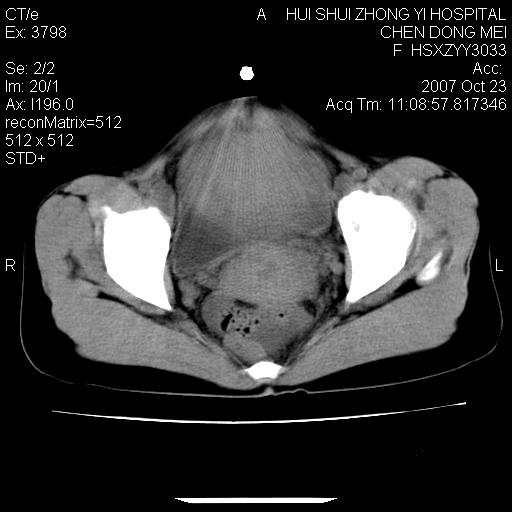

标题: CT10156:女.43岁,发现中下腹部包都块2年 [打印本页]

标题: CT10156:女.43岁,发现中下腹部包都块2年

发现中下腹部包都块2年。2年来月经不规律。

腹腔巨大软组织密度影,边缘光滑,包膜完整,内囊变坏死。腹膜后及盆腔内淋巴结肿大。结合病史考虑卵巢癌可能性大。

病变巨大,呈囊实性改变,包膜较厚且完整,内见分膈,周围脏器明显受压移位,病变与左侧附件关系密切,考虑来源左侧附件的囊腺瘤,不除外癌变可能;畸胎瘤可能性较小。

病变巨大,呈囊实性改变,包膜较厚且完整,内见分膈,周围脏器明显受压移位,病变与左侧附件关系密切,考虑来源左侧附件的囊腺瘤,盆腔内见肿大淋巴结,不除外癌变可能。